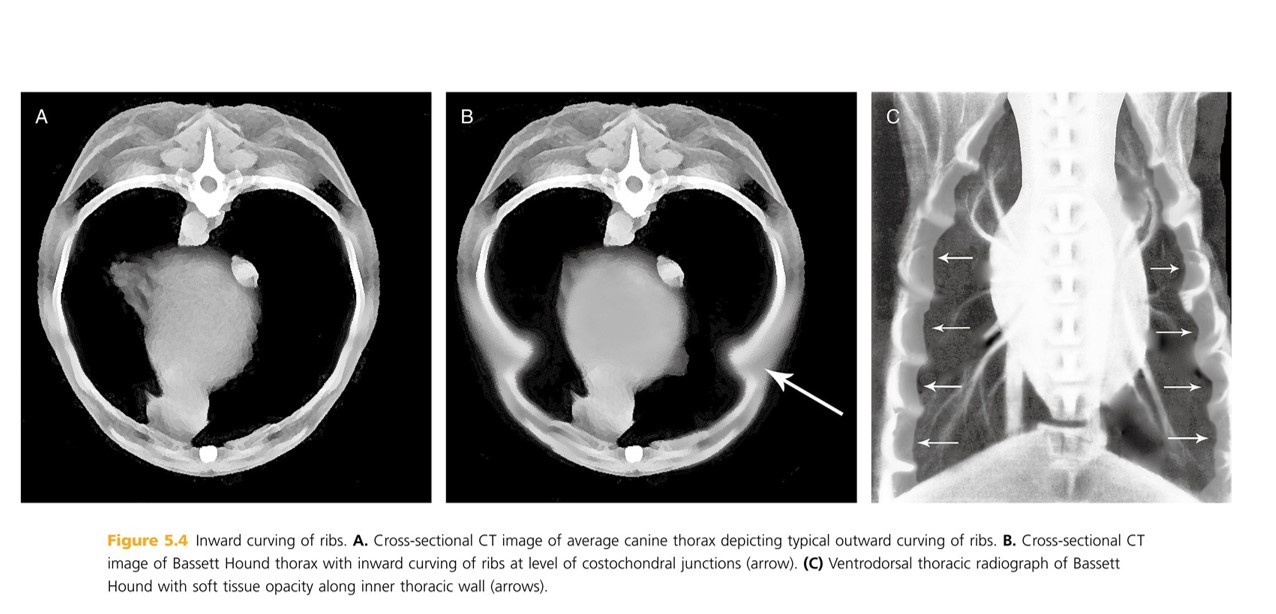

Ribs curve outward at spine, then inward, then outward, and finally inward again to join sternum. (Creates a double C shape in ____-____)

On ventrodorsal radiographs, inward curving ribs create soft tissue opacity along inner thoracic wall, which may mimic _____ ____

pg. 278 cross-section (CT image)

plureal effusion